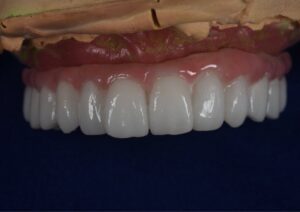

仮歯

最終仕上げはこのように想定しております。(シェードA2)

歯牙が長いので歯肉色で調整しようと思います。